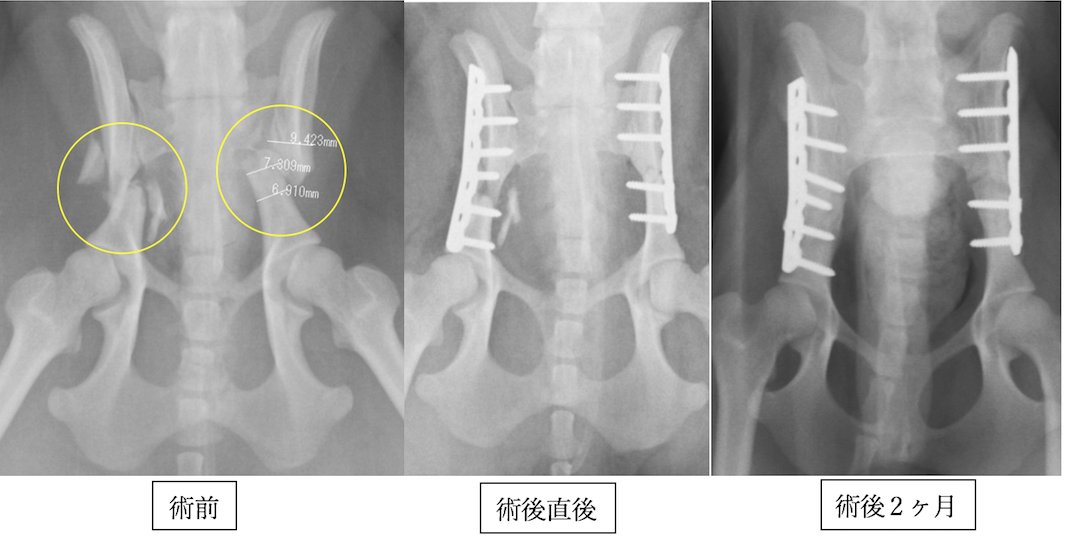

ポメラニアンの骨盤骨折です。両側であり、手術時間の短縮と固定力の強化のためにロッキングプレート・スクリュー(プレートとスクリューが固定されるシステム)を使用しました。プレート抜去はしなくても良いタイプです。